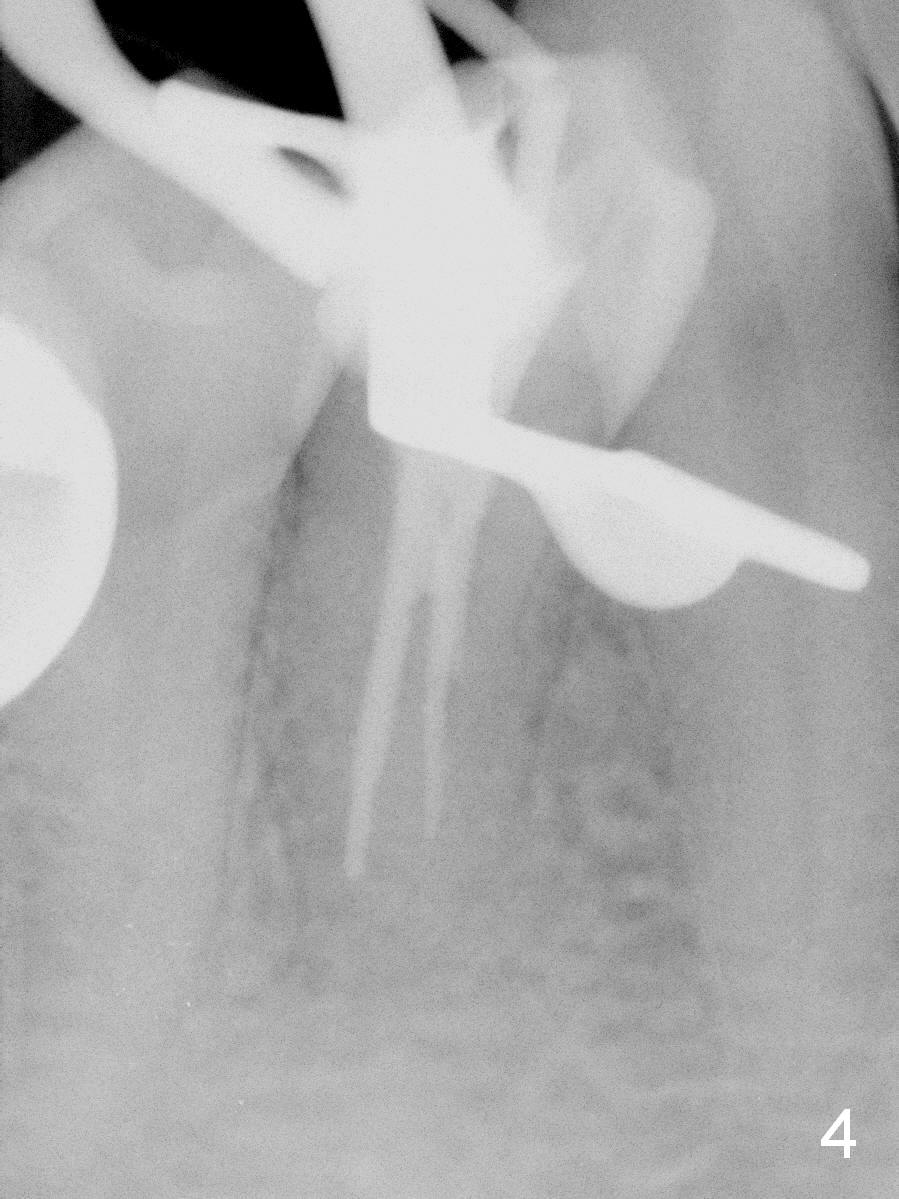

Further exploration finds a lingual canal (Fig.2), which is debrided until 30 hand file. When the canals are being filled with gutta percha and paste, the lingual canal is not filled (Fig.2). After removal of buccal gutta percha, the lingual canal is enlarged with 30/.04 rotary file and filled (Fig.4). The lingual canal is laterally condensed; composite build up is finished (Fig.5).

In fact CBCT has ben taken for #14 RCT and is reviewed prior to this case. If CT were reviewed, finding the extra canal would be easier (Fig.6 coronal section). It appears that the apical canals are blocked (Fig.7). The canal is split at the middle of the root, as shown in Fig.8,8' (axial upper section, as shown by the upper dashed line in Fig.6) and in Fig.9,9' (axial lower section, as shown by the lower dashed line in Fig.6). The buccal canal should not have been debrided with 40/.04 rotary file (30/.04 would have been better). In all, the tooth has two fused roots (Fig.3,9,9').